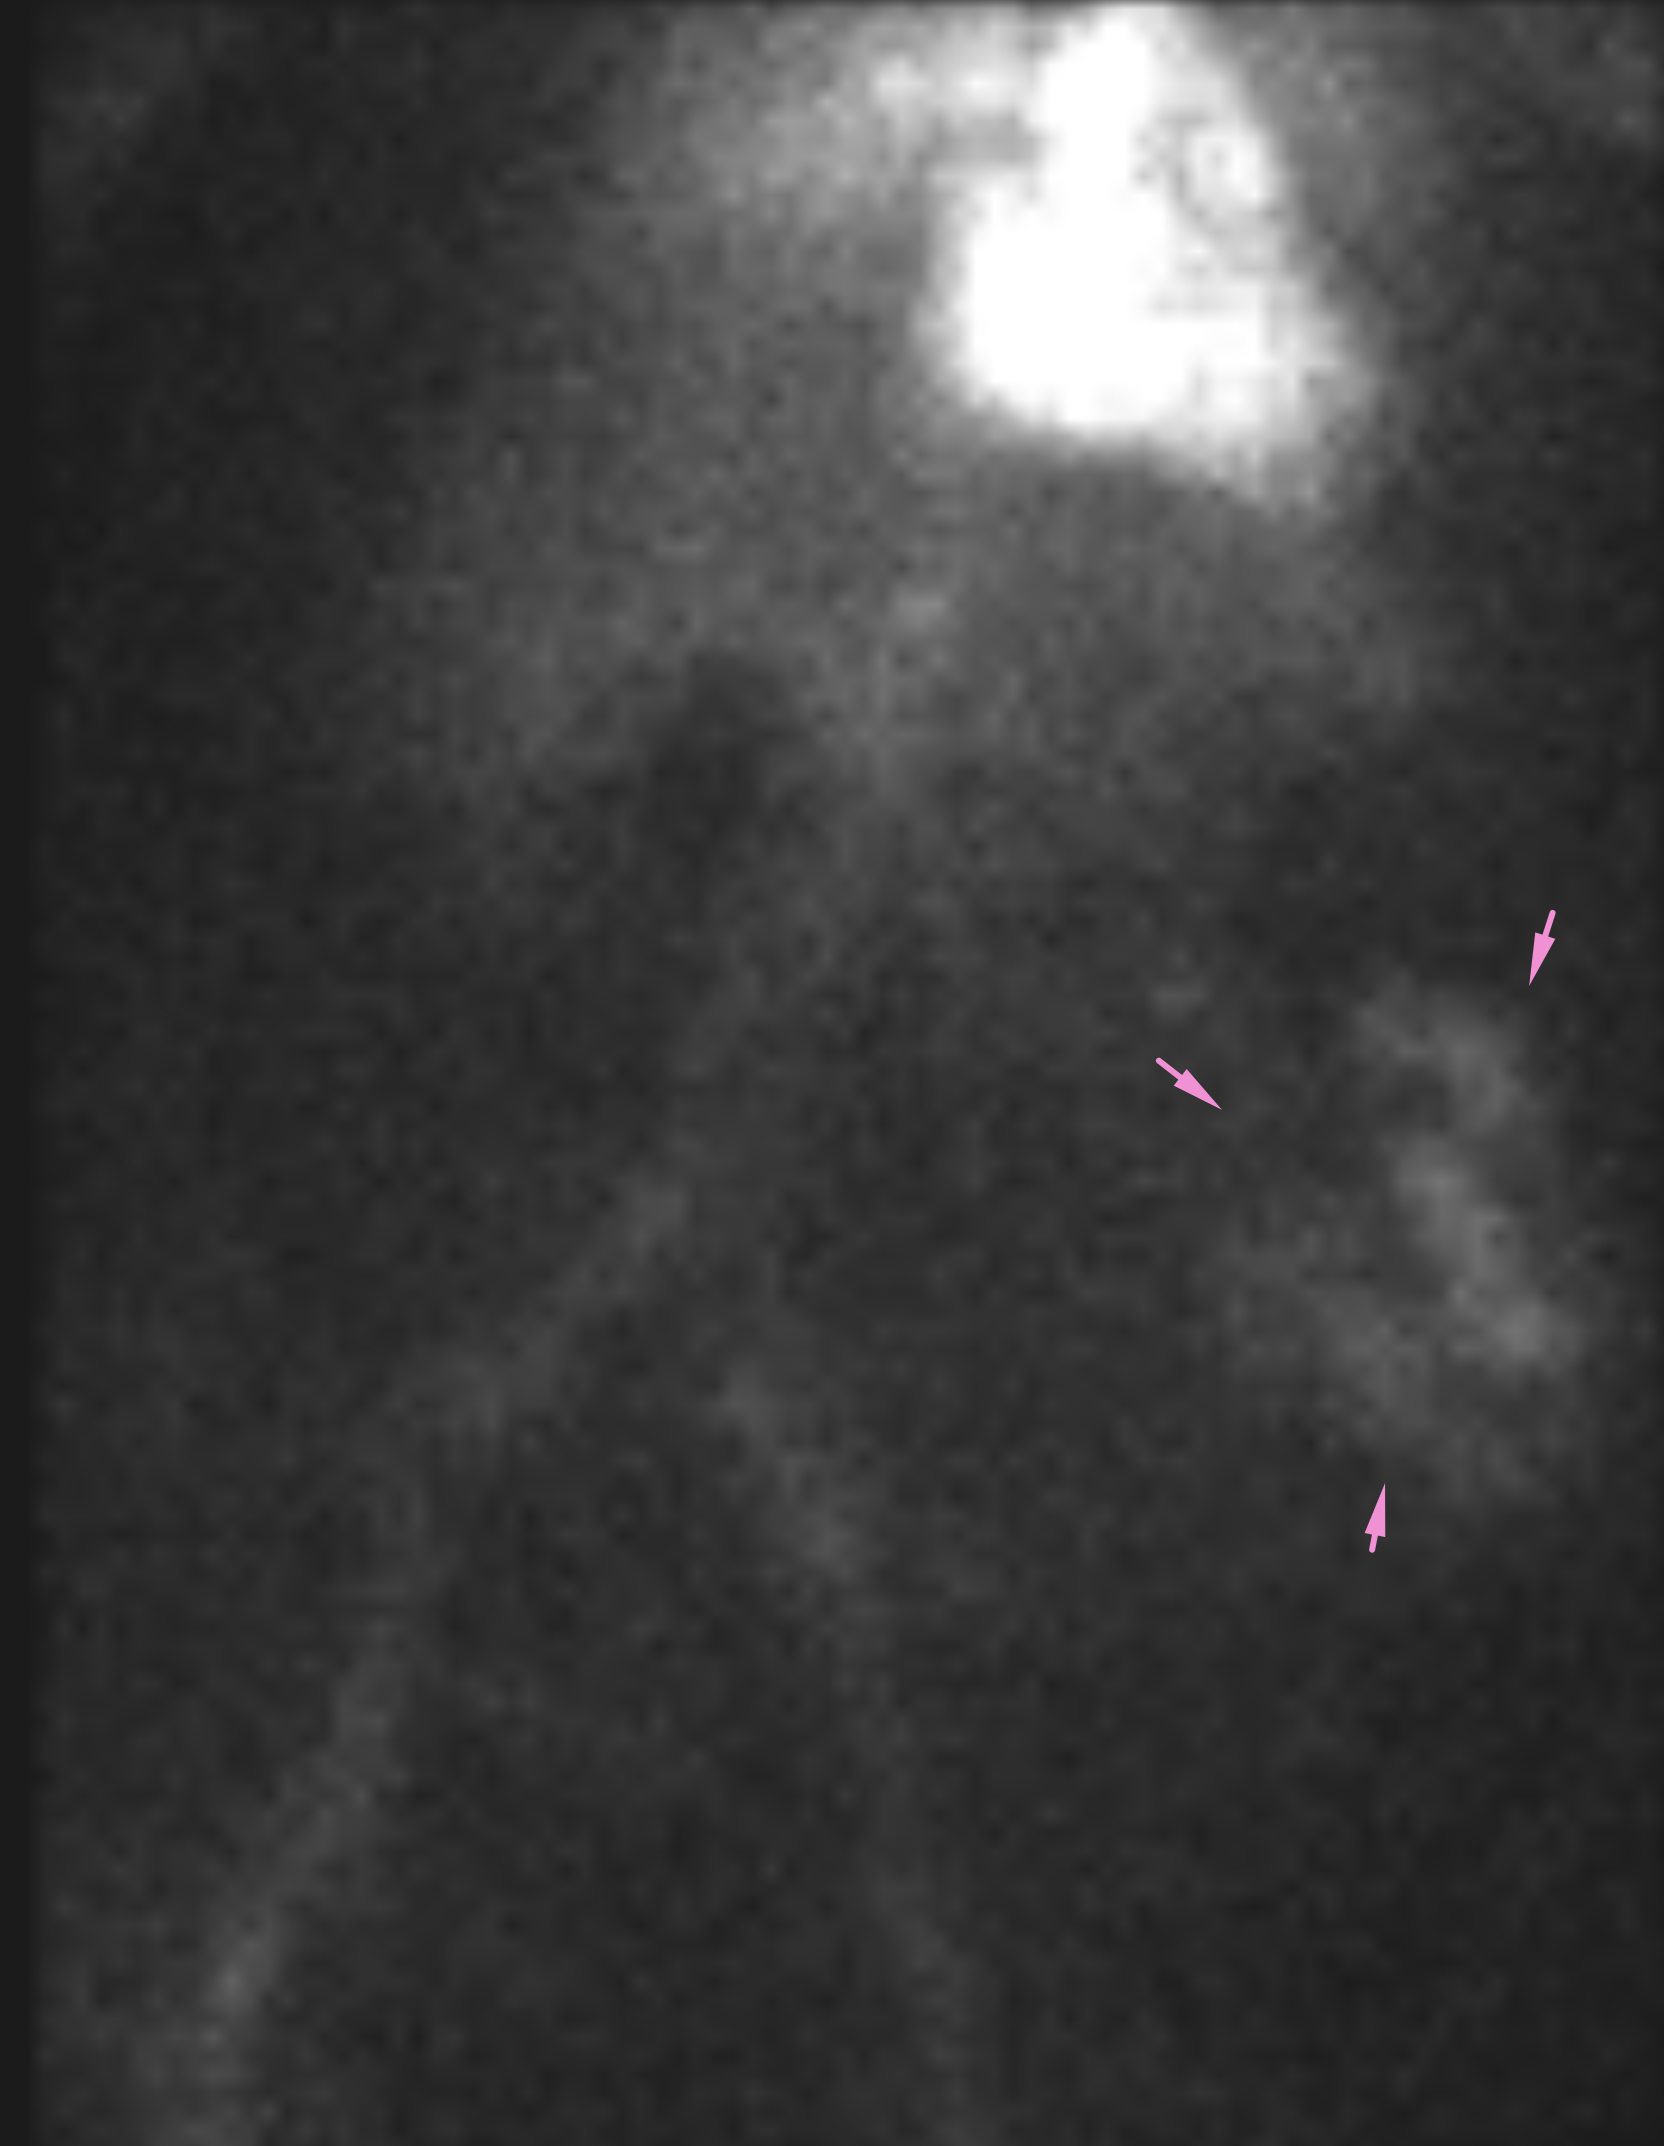

Age: 84

Sex: Female

Indication: Hematochezia with recent negative upper endoscopy and colonoscopy

Radiotracer: Tc99m labeled RBCs

Sample ReportPositive for active GI bleeding, likely originating within small bowel in the left lower quadrant.